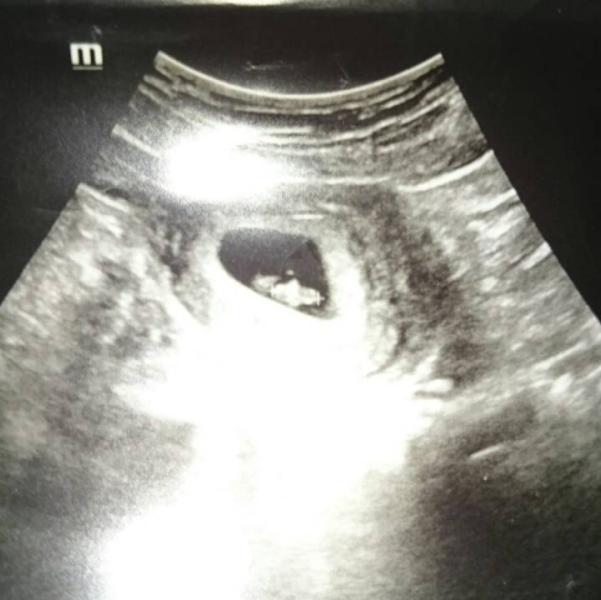

Вот и первое узи, все хорошо😇 6 недель-сердечко стучит, муж счастлив, а дочь плачет почему не двойня((( хочет сестренку, думала вопрос будет решен если будет двойня, папа то хочет сыночка. К вечеру объявила, ладно я не против если мальчик будет)))